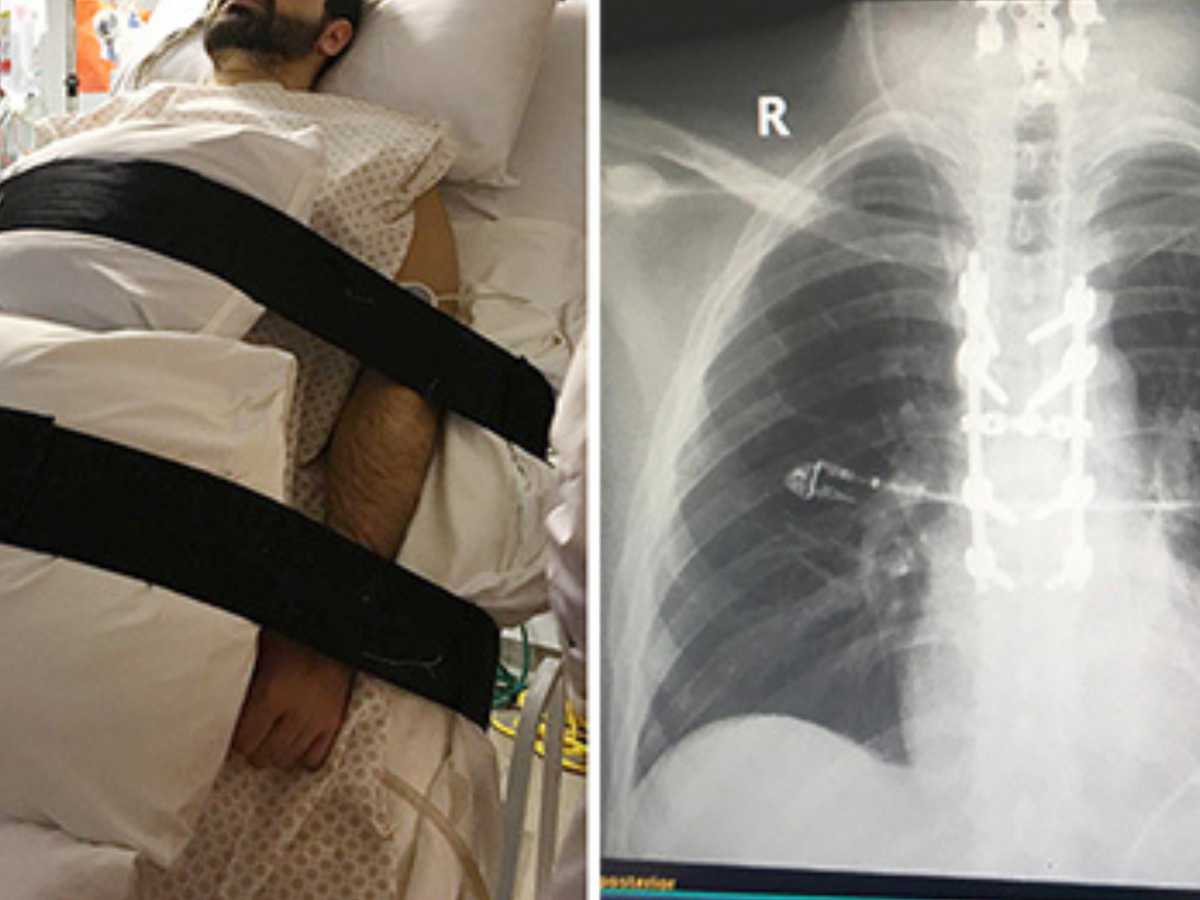

Foto: Reprodução/FAPERJ

Com isso, a polilaminina é aplicada diretamente na medula espinhal durante um procedimento cirúrgico. Ela forma uma espécie de malha que orienta os neurônios a se reconectarem, restabelecendo a comunicação entre as células nervosas, segundo a FAPERJ.

No entanto, há um detalhe importante. O tratamento consiste em uma aplicação cirúrgica única no ponto da lesão, geralmente dentro de até 72 horas após o acidente, aumentando as chances de recuperação. Mas os avanços dos estudos indicam que, no futuro, pessoas paralisadas há anos possam recuperar a mobilidade.